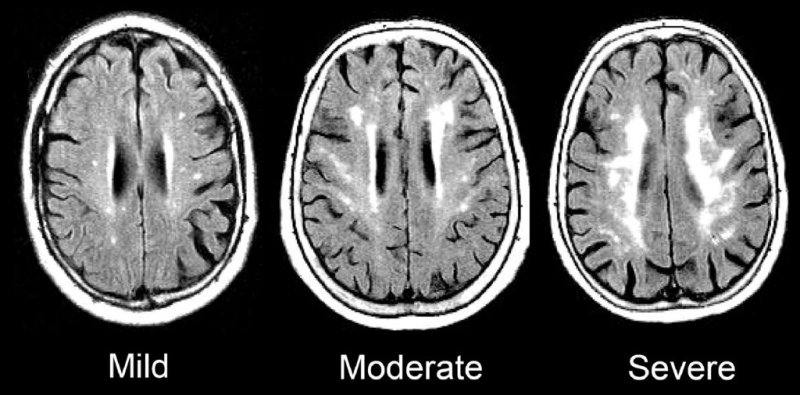

Ricercatori finlandesi hanno studiato le cause di morte dei musicisti classici in Finlandia. Tra questi, la mortalità era inferiore per le malattie cardiovascolari rispetto all'intera popolazione, ma la mortalità per demenza, come il morbo di Alzheimer...